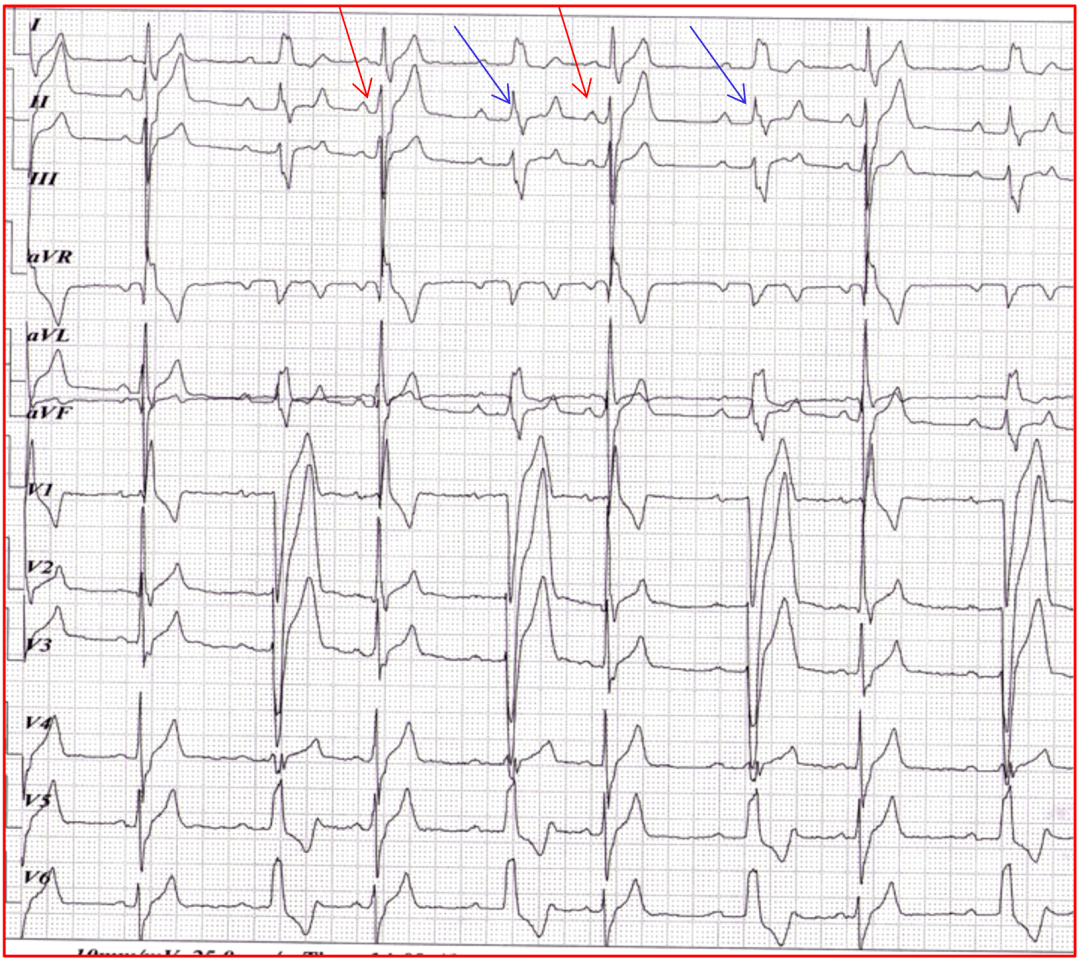

SIQIIITIII心电图

肺栓塞心电图改变之siqiiitiii

2.siqiiitiii 改变

心电图:sⅠqⅢtⅢ

特异性高的心电图变化包括siqiiitiii征,右胸导联深大t波倒置,右室高

1~0.2 mv,有siqiiitiii,si变小(图2,图3).